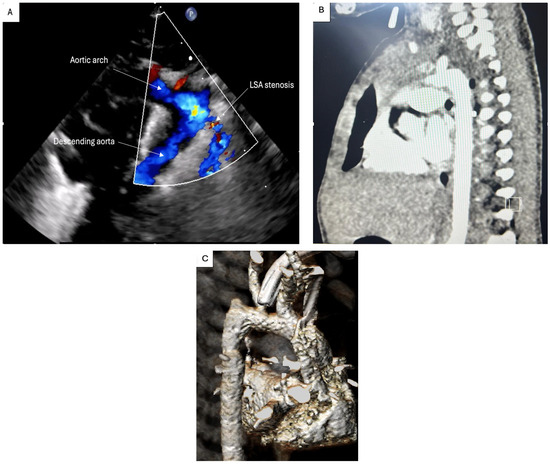

2. Case Presentation